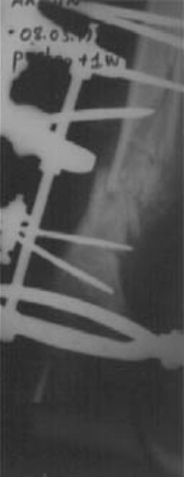

2. Gevşek Atrofik Psödoartroz

Bu tip psödoartrozlar genelikle atrofik olarak kabul edilmelidir. Her ne kadar İlizarov yayınlarında, psödoartroz bölgesindeki atrofiyi monofokal kompresyon-distraksiyon osteogenezisi (akordion tekniği) ile aktiv ettiğini bildirse de Anglosakson literatürü bölgenin primer olarak greftlenmesini önermektedirler. Bizim tecrübemizde bu bölgenin primer greftlenmesi yada post operatif takip dönemlerinde bir veya iki kez kemik iliği enjeksiyonları yaparak psödoartroz hattının aktive edilmesi ve monofokal kompresyon osteogenezi uygulanmasıdır.